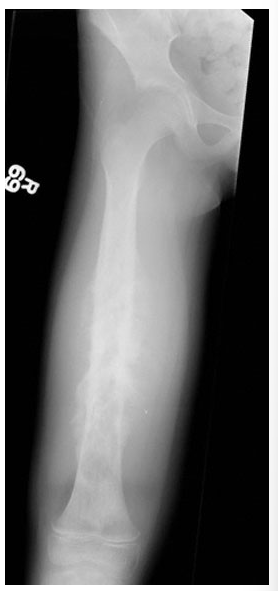

12yo girl with thigh pain for 2 months, worsening in past 10 days with a low fever for 1 week. what is it and what is the most consistent natural history of this disease?

osteosarcoma, metastasis to the lungs. high mortality rate, even with surgical resection, because small undetectable cells may have already metastasized.